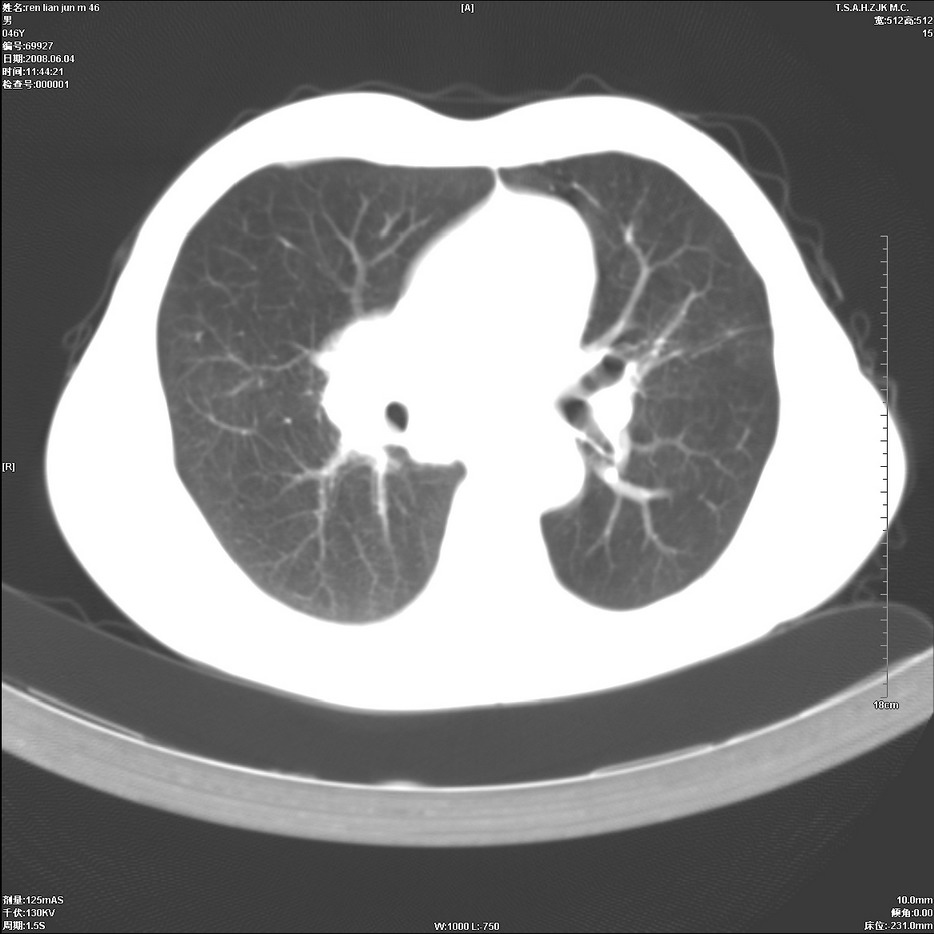

以下是引用qiu999在2008-6-5 17:14:00的发言:[br]考虑右肺中心型肺癌.颅内应做增强检查.

以下是引用形影不离在2008-6-5 19:18:00的发言:[br]右肺中心型肺癌并纵隔及左侧腋窝淋巴结转移,颅内应做增强检查。

以下是引用杀毒软件在2008-6-5 18:33:00的发言:[br]支持考虑右肺中心型肺癌,颅内病变是不是转移,不好说